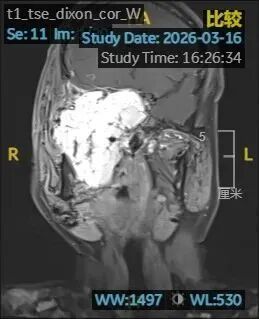

3月16日傍晚,小张再次发生鼻腔大出血,血红蛋白跌至78g/L,这意味着他全身血液已流失超过一半。神经外科秦宣锋主治医师团队于当晚21:00为小张紧急施行DSA造影及双侧颌内动脉栓塞术,暂时控制了出血。但肿瘤本身仍在持续渗血,若不从根源切除,小张随时可能面临生命危险。

手术整整持续12小时。手术结束时,小张的血红蛋白仍只有41g/L,他被直接转入重症监护室。术后核磁显示,肿瘤已基本切除。

术后核磁显示肿瘤已基本切除